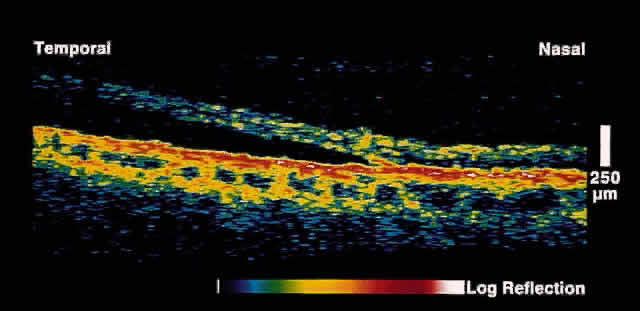

Initial studies using postmortem eyes showed good correlation between OCT images and histologic sections. Subsequent in vivo analysis demonstrated the ability of OCT to image the substructure of the retina. Figure 1 shows an OCT image of a normal fovea and optic disc taken along the papillomacular axis. Anatomic features such as the fovea, optic disc, and retinal profile are evident. The vitreoretinal interface is noted by the contrast between the nonreflective vitreous and the reflective surface of the retina. The foveal center demonstrates normal retinal thinning and has a characteristic pit to its contour. The optic disc demonstrates normal nerve head contour and cupping. The retinal nerve fiber layer, inner plexiform layer, outer plexiform layer, photoreceptor layer, choroid, and sclera are all well delineated.

Fig. 1. Color photograph of normal fundus. The white line indicates the area of retina and optic disc scanned on the corresponding OCT in B. B. OCT image through papillomacular bundle shown in A. The vitreoretinal interface, individual retinal layers, choriocapillaris, foveal contour, and optic disc are well delineated.

The posterior aspect of the neurosensory retina is bounded in the OCT images by a highly reflective red layer about 70 microns thick that represents the choriocapillaris and retinal pigment epithelium (RPE) layer. In vivo choriocapillaris thickness by OCT is greater than that of histologic sections because of postmortem blood depletion and artifacts in tissue processing. The high contrast between the choriocapillaris/RPE layer and the neural retina in OCT images provides a useful boundary for use in measurements of retinal thickness. Retinal blood vessels are evident in OCT images by their shadowing of deeper retinal structures. The region just anterior to the choriocapillaris/RPE layer is typically weakly reflective and corresponds to the photoreceptor layer. The highly reflective red layer at the inner margin of the retina corresponds to the nerve fiber layer. In the OCT image taken along the papillomacular axis (see Fig. 1), the thickness of the nerve fiber layer increases from the fovea to the optic disc. Circular tomographs taken around the disc demonstrate modulations in thickness consistent with the superotemporal and inferotemporal bundling of the nerve fibers. Because retinal detail is so exquisitely imaged by OCT, this imaging modality can be applied to a large number of clinical entities.